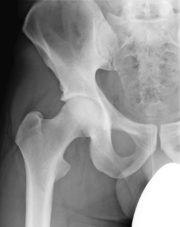

Hüftgelenksarthrose (Coxarthrose)

Unter Hüftgelenksarthrose (Coxarthrose) versteht man einen Verschleiß des Knorpelüberzuges an Oberschenkelkopf und Hüftgelenkpfanne. Normalerweise gewährleistet der intakte Knorpel durch seine glatte Oberfläche eine schmerzfreie Bewegung im Hüftgelenk. Durch den defekten Knorpel kommt es zu vermehrter Reibung, welche Schmerzen verursacht. Patienten mit Hüftarthrose verspüren meist einen Schmerz im Bereich der Leistenregion, begleitend kann eine Schmerzausstrahlung in den Oberschenkel bestehen. Durch die vier Kardinalsymptome Nachtschmerz, Ruheschmerz, Anlaufschmerz und einer eingeschränkten Gehstrecke ist die Lebensqualität der Patienten deutlich eingeschränkt. Begleitend besteht auch eine Bewegungseinschränkung des Hüftgelenkes, so kann bereits das Anziehen von Socken oder Schuhen erschwert sein.

Die Ursachen der Arthrose sind vielfältig. Meist besteht aber ein altersbedingter Verschleiß des Knorpels. Andererseits kann eine nicht erkannte Hüftdysplasie im Kindesalter durch eine ungünstige Gelenksituation zu einer vorzeiten Hüftarthrose führen. Bei Rheumapatienten kommt es hingegen zu einer fehlgesteuerten Immunabwehr gegen das eigene Gelenk. Durch die Entzündungsreaktion wird das Gelenk zerstört. Eine andere Ursache kann eine Durchblutungsstörung des Hüftkopfes durch die langfristige Einnahme von Cortison oder z. B. übermäßiger Alkoholgenuss sein. Hierunter kommt es zu einem Absterben des Hüftkopfes (sog. Hüftkopfnekrose).

Durch Unfälle kann es zu Schädigungen des Hüftkopfes oder Gelenkpfanne kommen. Insbesondere bei fehlerhaft ausgeheilten Brüchen mit Beteiligung des Knorpels kommt es zur Arthrose.